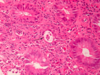

What do you see here?

- Normal colonic epithelium: irritable bowel syndrome (IBS) can present like this

- IBS is characterized by chronic, relapsing abdominal pain, bloating, and changes in bowel habits

- Despite very real symptoms, gross and microscopic evaluation is normal in most IBS patients